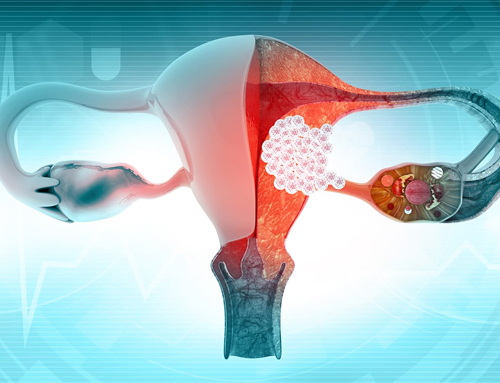

Dr. Mashru has completed his MBBS, MS in General Surgery and DrNB in Surgical Oncology, along with prestigious fellowships such as FIAGES and FALS (Oncology). His training includes extensive exposure to GI oncology, breast cancer surgery, thoracic oncology, urological cancers, head and neck cancers and gynecological oncology, with hands-on experience in both conventional and advanced surgical techniques.